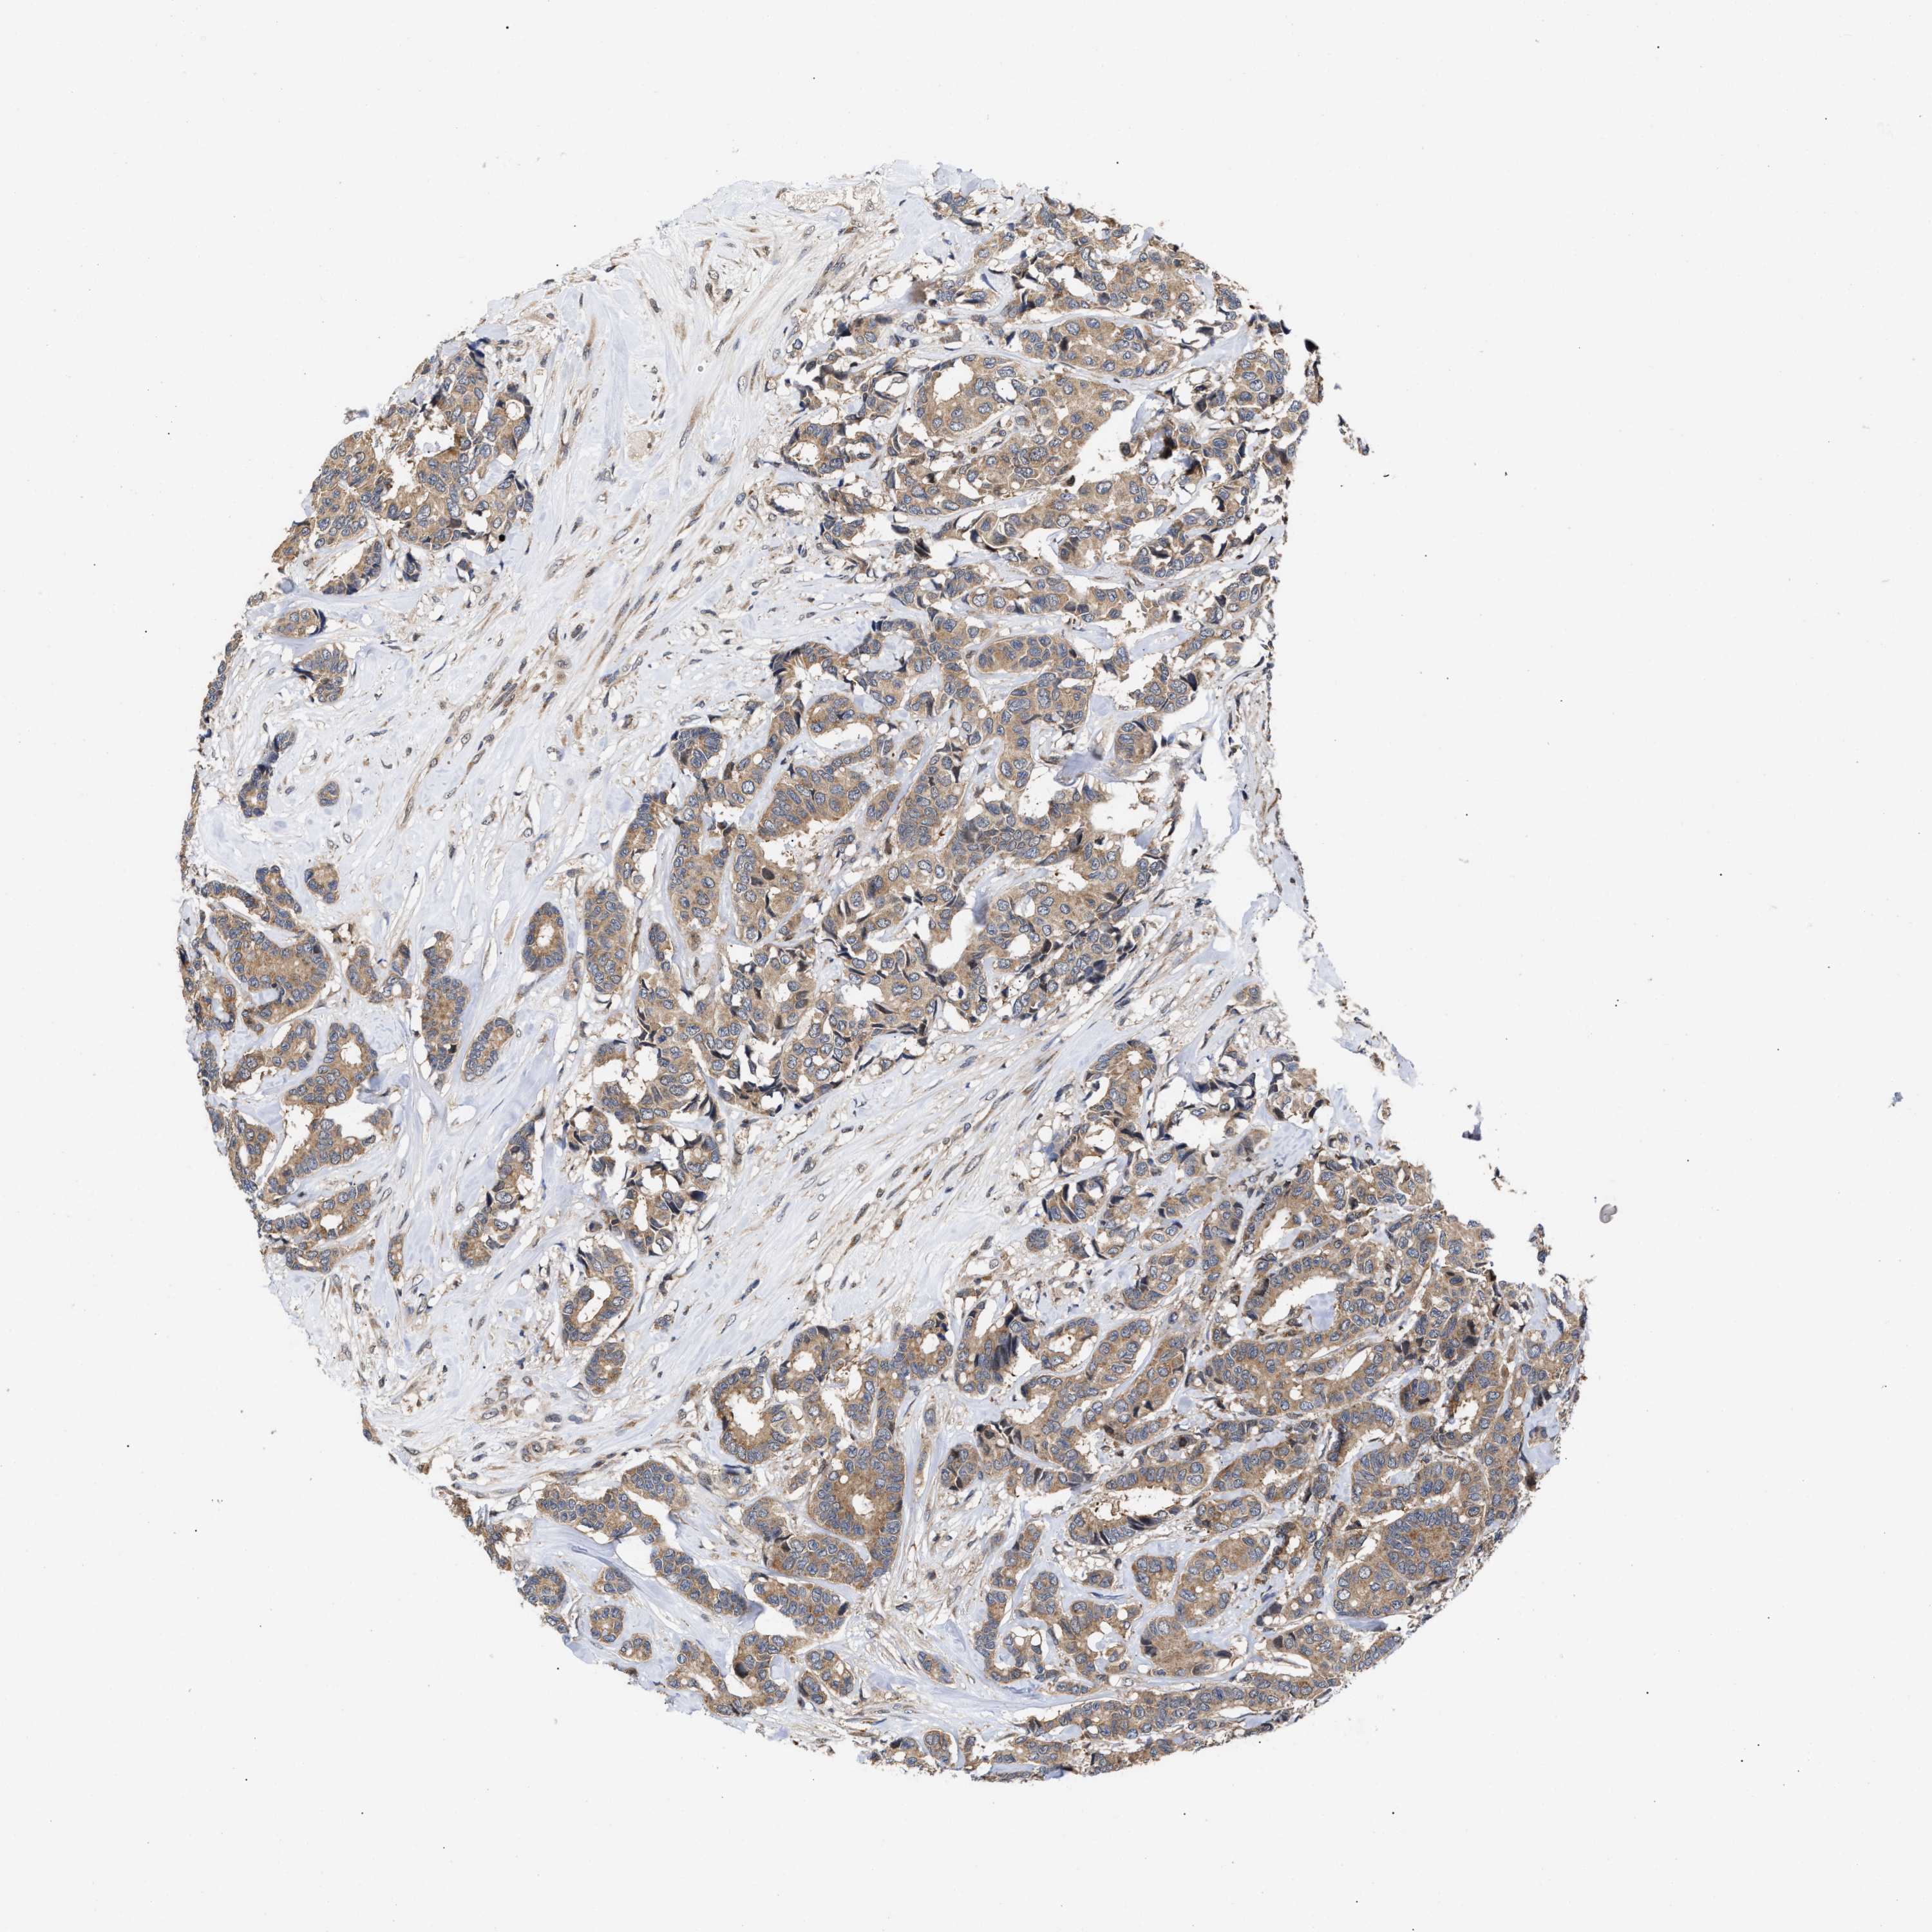

CANCER BREAST CANCER Show tissue menu

BRCA TCGA BRCA VALIDATION PROTEIN EXPRESSION